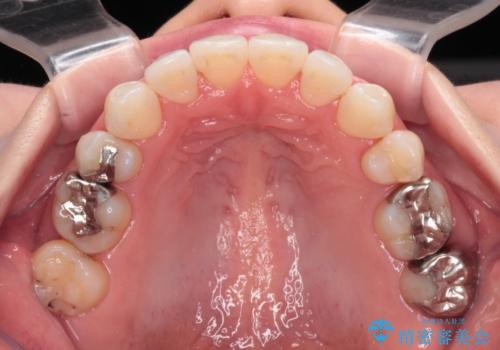

イレギュラーな大臼歯抜歯矯正であったため、治療期間の長期化が想定されましたが、何とか3年ちょうどで終えることができました。

今後は目立っている銀歯を中心にセラミッククラウンなどへ交換していく予定です。